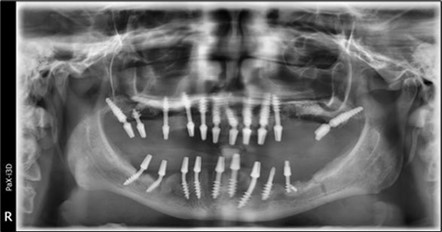

In the upper anterior region, after extractions and regularization, marginal gingival connective tissue located palatine is harvested for use in augmenting the anterior area. This tissue is de-epithelized with a scalpel and kept in saline solution until used (Figure 4, Figure 5). The implants used are BCS corticobasal implants in areas with significant bone loss, and TPG compression implants, both from Dr. Ihde Dental AG, for post-extraction areas and regions with a large amount of trabecular bone but of poor quality (D3-D4). Both types of implants have a polished surface to reduce bacterial adhesion, and they feature a 2mm prosthetic collar that can be bent to parallelize the prosthetic part of the implant according to prosthetic requirements (Figure 3). The only exception to this parallelization through bending is the TPG implant in the maxillary-sphenoid fusion area (quadrant 2), were, due to lower torque, a prefabricated parallelization sleeve with a 25° angle was preferred. This sleeve was cemented before the impression was taken (Figure 3).

A total of 11 implants is placed in the maxilla, including compressive TPG implants with a polished surface in the maxillary-sphenoid fusion area (Figure 3, Figure 9). Similarly, in the anterior region, final fixation is achieved in the nasal cortex, and BCS corticobasal implants are added in areas with massive bone loss in the frontal region (Figure 3, Figure 8, Figure 11). Additionally, in the palatal sinus cortical area, with the aim of avoiding the addition and sinus lift zone where the second cortical bone no longer exists, 3 implants are placed, 2 in quadrant 1 and 1 in quadrant 2 (Figure 3, Figure 8). Through the Caldwell-Luc sinus lift procedure, the sinus cortical bone is displaced to allow the placement of the graft material and elevation of the sinus membrane. This sinus cortical is no longer recreated at the junction of the graft material and mucosa-sinus membrane, making it impossible to place a corticobasal implant, which relies on the second cortical bone. In the distal mandibular area, after the removal of two stage implants due to massive destruction in quadrant 3, implant placement distal to the mylohyoid line is not possible, as in quadrant 4 (Figure 10). A re-intervention occurs after 5 months to stabilize the area (Figure 12, Figure 14). Also, at the moment of fixation, the tip of one implant fractures, and the decision is made to leave it in place due to regional bone destruction, in order to avoid enlarging the bone defect.

In the interforaminal area (Figure 3, Figure 13), 6 corticobasal implants are also placed. The increased number of implants is due to the poorly represented distal area that needs to be compensated.

Figure 3.Panoramic pictures after removal of implants affected by peri-implantitis, extractions, alveolar crest regularization, and insertion of corticobasal and TPG implants (07.2022)